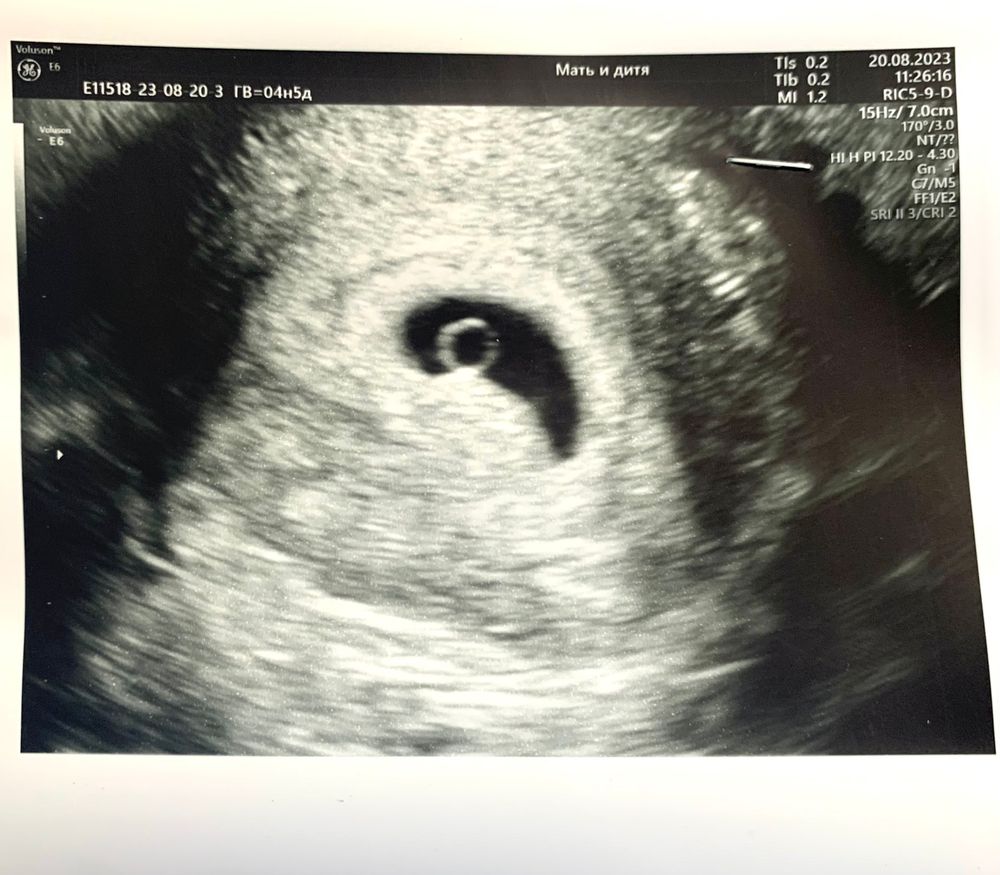

Я БЕРЕМЕННА !Ну вот и я с ними сегодня впервые столкнулась🙈 Утром проснулась, а на бумажке темно-коричневые выделения, через пару часов их уже почти не было… выделений нет, а переживания есть) Вместо планового УЗИ на 21ДПП поехала сегодня. По итогу мы имеем маточную беременность и уже есть желточный мешочек💛

ПЯ 9.1мм

ЖМ 2.7мм

Отличное плодное яйцо! Отличный ж.мешочек! Отставить переживания! Все будет хорошо!!!

Очень красивая фотография красивого малыша☺️пусть растёт и развивается 🤞🙏

Поздравляю Вас❤️❤️❤️ Растите здоровыми! Такая фотка классная, как глазик 😁

Очень красивое «колечко» ❤️🙏🏼 тоже уже пережила эти выделения, всё будет замечательно! 🙏🏼🙏🏼🙏🏼🧿